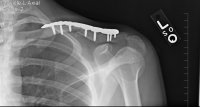

Busted right clavical, two concussions, busted tailbone, multiple deep dirt burns. Only weight 130lbs when I hit the shit I don't get that busted up.